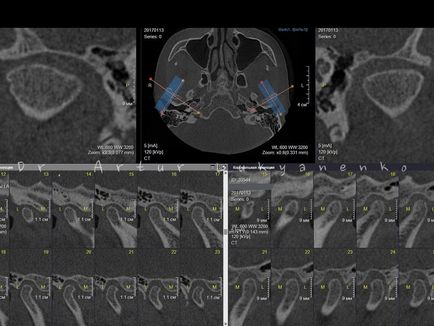

Stock 2. CBCT diagnosztizált távoli pozíció az ízfelszínekkel a mandibula, különösen a bal oldali a szokásos összefogazódása.

Stock 2. CBCT diagnosztizált távoli pozíció az ízfelszínekkel a mandibula, különösen a bal oldali a szokásos összefogazódása.